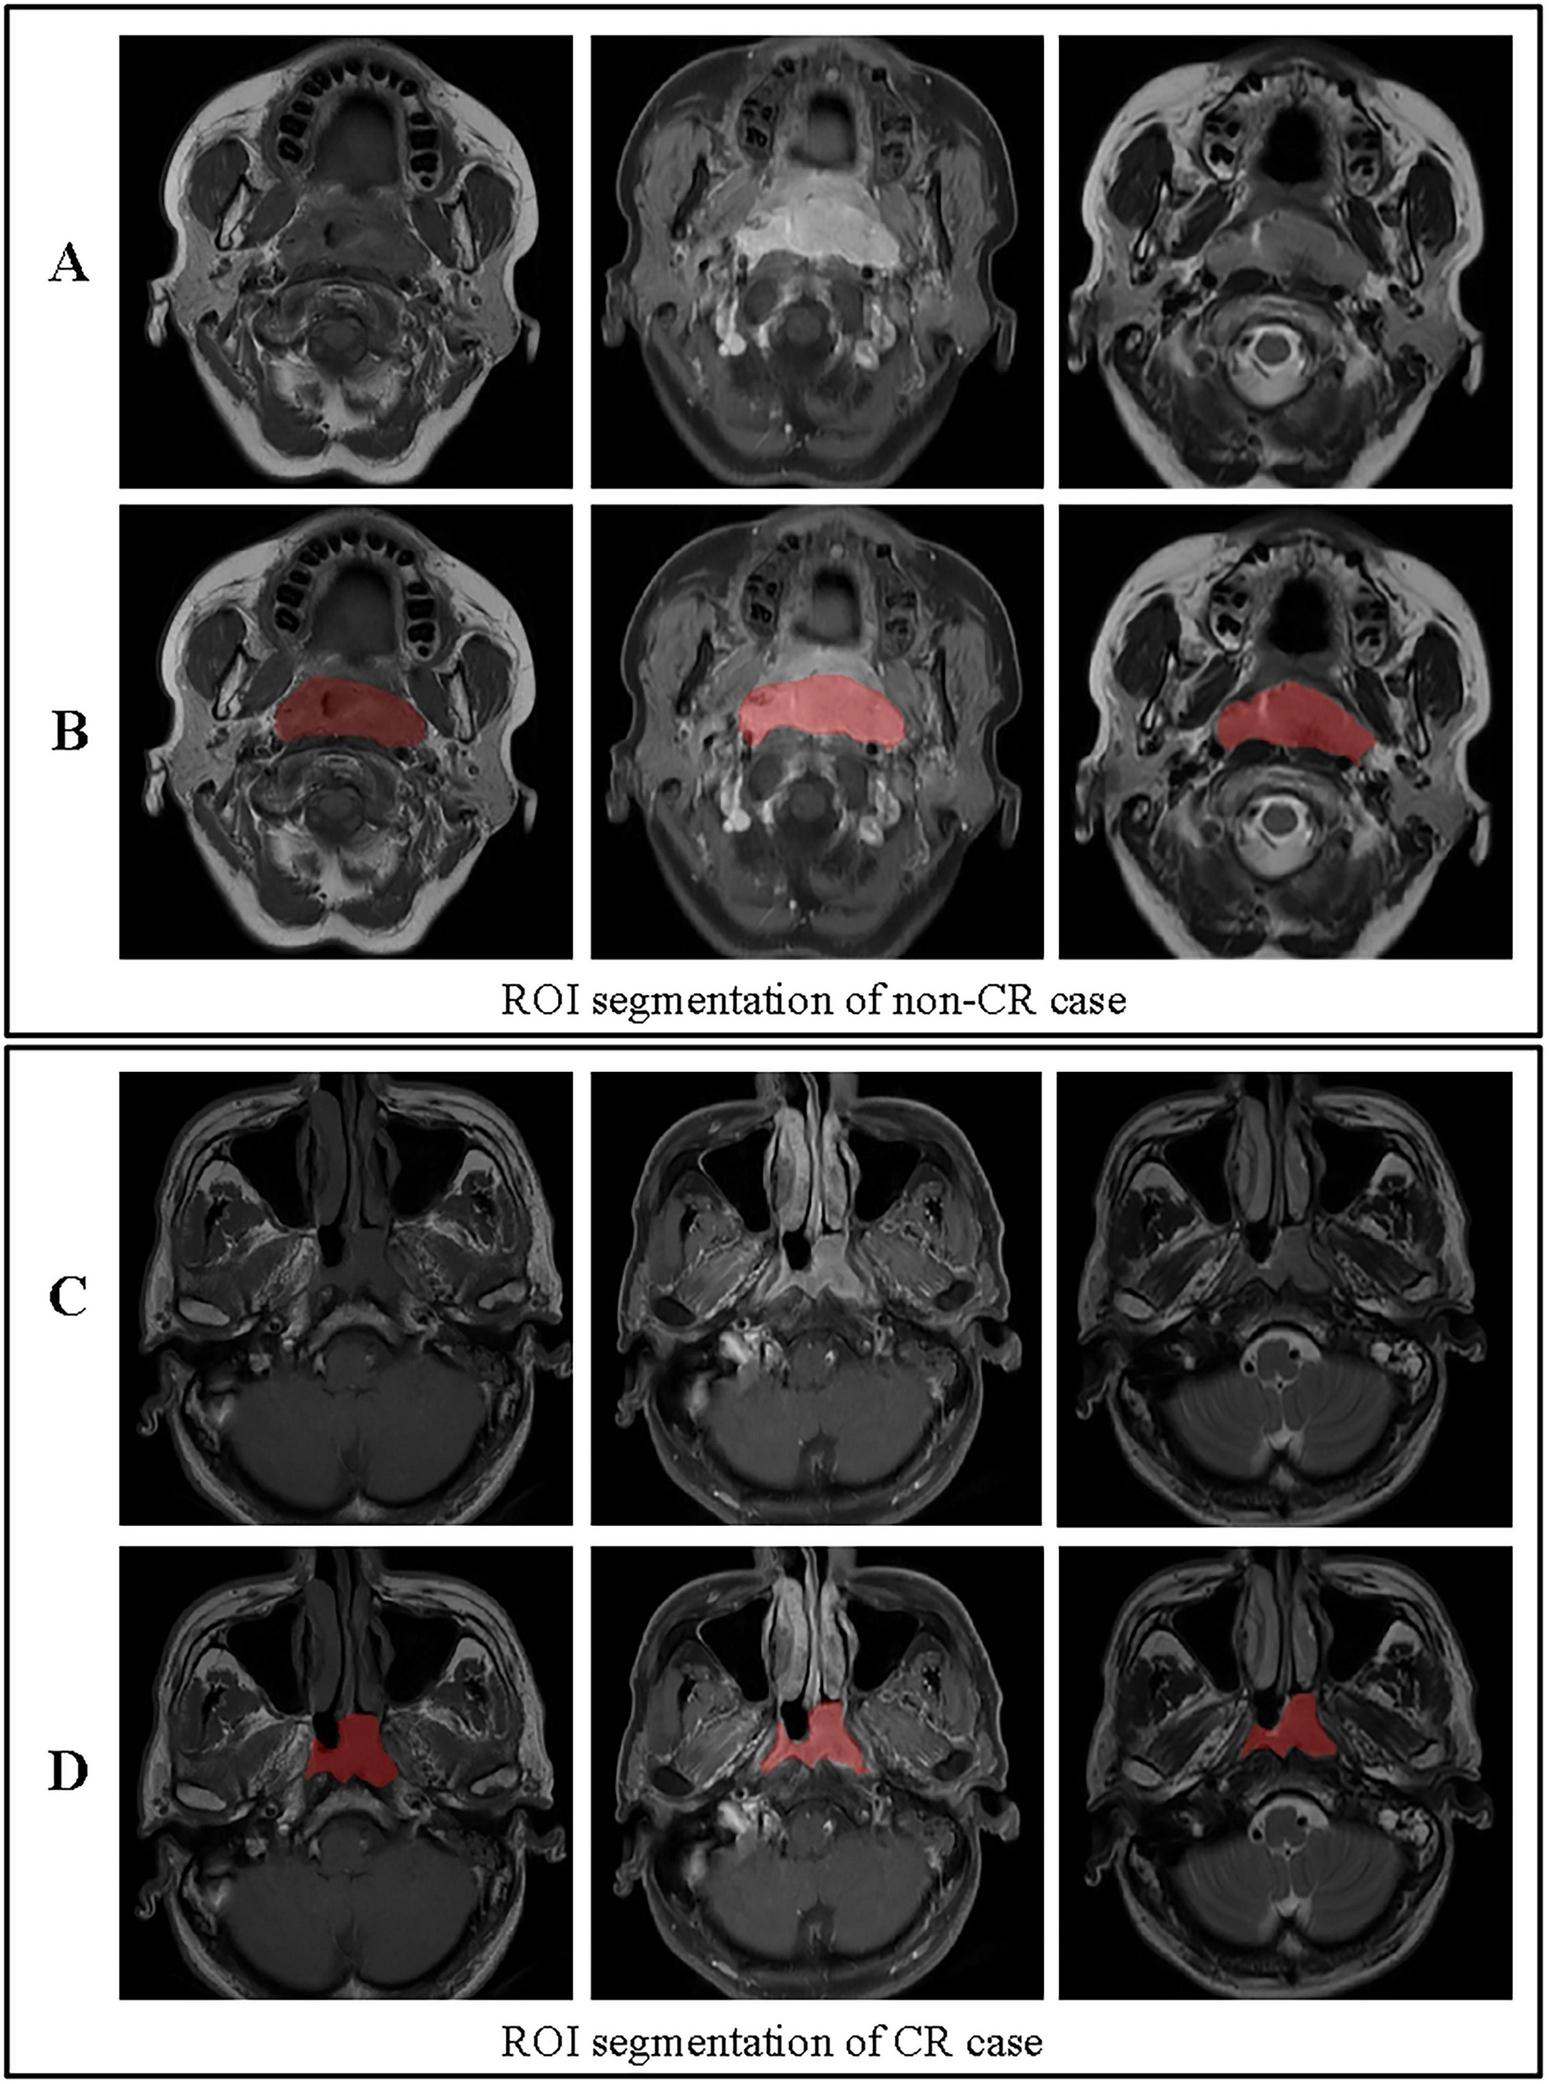

Volumes of interest (VOIs) were manually delineated on the primary nasopharyngeal tumor on all sequences (T1WI, T2WI, and CE-T1WI) by two radiologists (R1 and R2, with 10 and 15 years of experience in head and neck imaging, respectively) using ITK-SNAP software. Both readers were blinded to the clinical outcomes and followed a pre-defined segmentation protocol that specified the inclusion of the entire gross tumor volume while excluding obvious necrotic regions, vessels, and adjacent normal tissue as shown in Figure 3 (27). To assess inter-observer variability, both radiologists independently segmented a randomly selected subset of 30 patients. The intraclass correlation coefficient (ICC) was calculated for each feature extracted from these duplicate segmentations. Features with an ICC > 0.85 were considered robust and retained for further analysis. The remaining cases were segmented by R1 and reviewed by R2; any discrepancies were adjudicated by a senior radiologist (20 years of experience) to establish a consensus segmentation gold standard (28).

FIGURE 3

ROI segmentation for non-CR and CR cases. (A) Original images for a non-CR case, from left to right: T1, contrast-enhanced T1-weighted, and T2 sequences. (B) ROI segmentation for the non-CR case on T1, contrast-enhanced T1-weighted, and T2 images. (C) Original images for a CR case, from left to right: T1, contrast-enhanced T1-weighted, and T2 sequences. (D) ROI segmentation for the CR case on T1, contrast-enhanced T1-weighted, and T2 images. This figure demonstrates the differences in ROI segmentation between non-CR and CR cases, highlighting the segmented tumor regions in red.